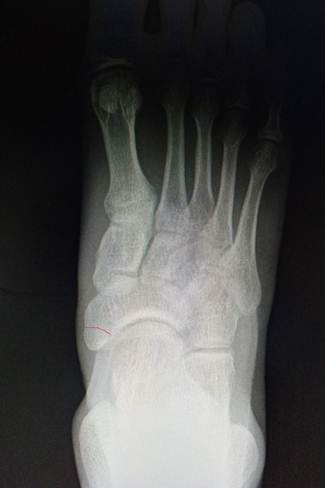

Слева

прямой снимок стопы ребенка 12 лет, апофиз ладьевидной кости тольок начал

прослеживаться (помечен красной стрелкой). Справа прямой снимок стопы ребенка

16 лет, полное срастание апофиза ладьевидной кости с основным костным массивом.

Красной линией отмечена локализация зоны просветления, которая наблюдается в

случае формирования os tibiale externum.